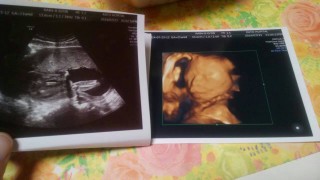

頭の大きさは5センチ以上になってました。 胎動も少しづつわかるように(^ω^) そして性別。 女の子みたいです!ネットの性別判断(つわりが少なければ男とか右の脈が強ければ女~とか医学的根拠が無いらしいアレです笑)それでは完全に男だったのに! やっぱり関係無いのかなー? しかしまだ確定じゃないので隠している可能性もあります(*^o^*)どちらでも良いので早く性別が知りたい!!! 行っている病院では2Dエコーしか無いので再来週に違う病院にて4Dエコーしてもらいます。 その時に性別わかるかな笑

6ヶ月検診時にもらったエコーです。

性別はまだわからなかったですが

こちらを向いてニコッと笑ってくれています☆

写真には右手がちょこんと乗っています。

なんだかアゴがでているのか?

そしたら旦那に似ていて嬉しいです☆

体重337グラム